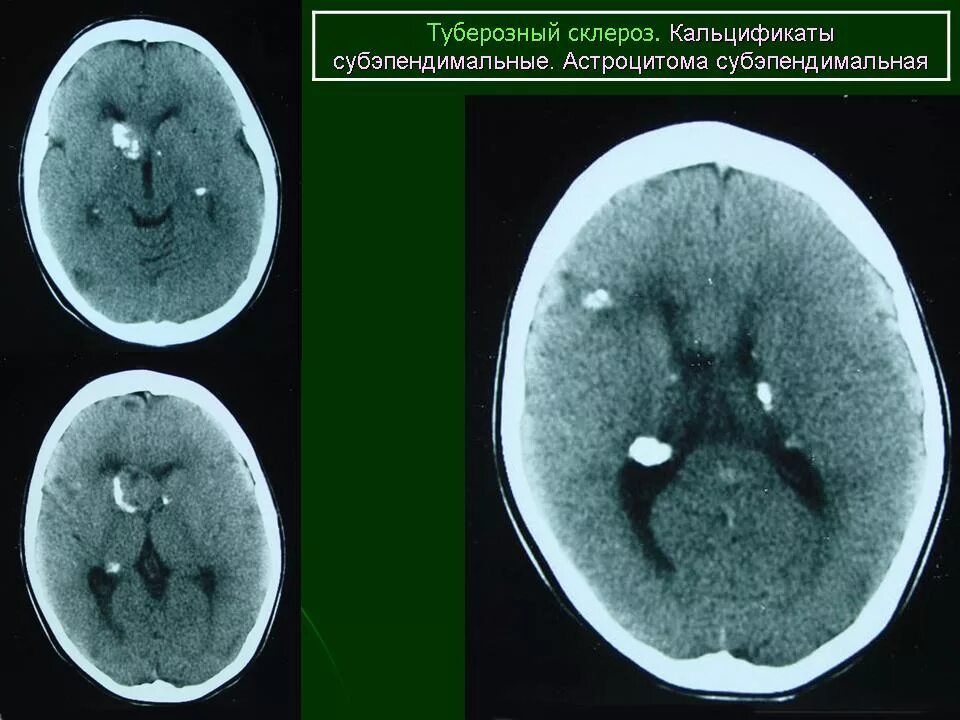

Туберкулезный склероз